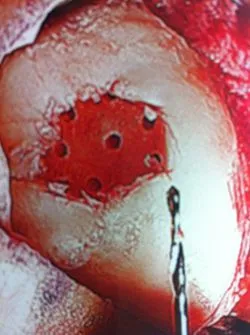

Series of Pics of Microfracture of large OCD of the Talar Dome

Pic of OCD after preparation and debridement .

Measuring the size and depth of the OCD.